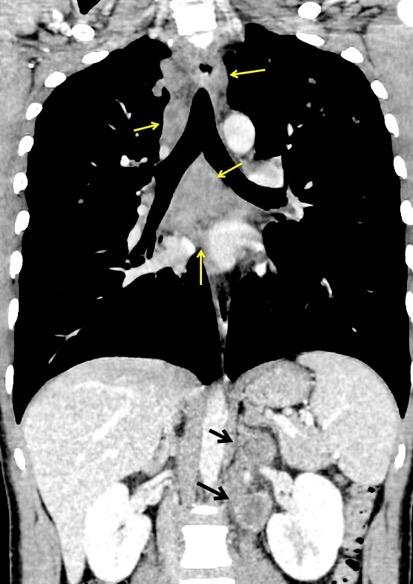

Ganglios retroperitoneales (flechas negras)

germinales del testículo izquierdo Nódulos pulmonares múltiples. (flechas verdes). Ganglios paratraqueales. (flechas amarillas). Dudoso ensanchamiento retrocrural (flechas negras)

Panda A et al. “Straddling Across Boundaries”. Thoracoabdominal Lesions: Spectrum and Pattern Approach. Curr Probl Diagn Radiol, 2015